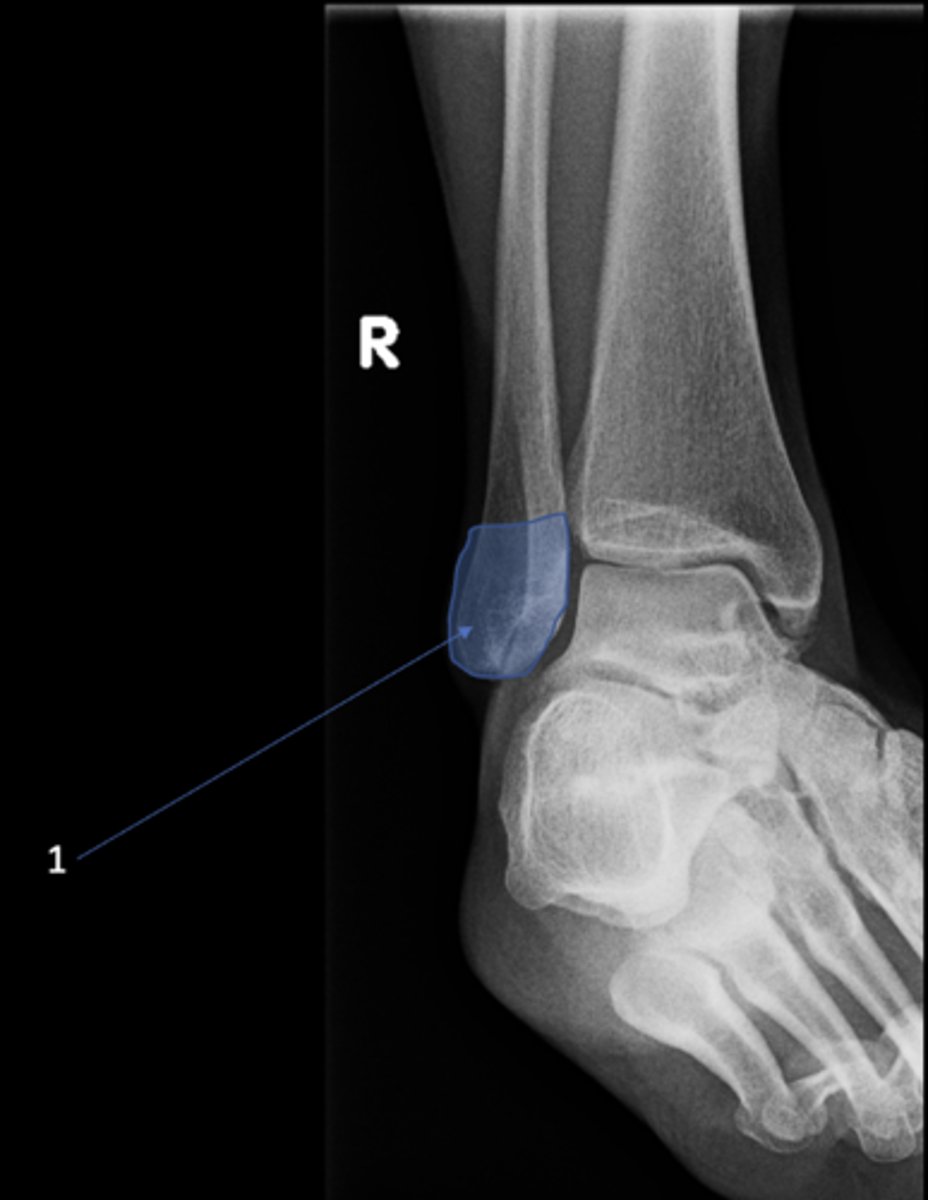

Right posterior superior iliac spine

ID 11

<p>ID 11</p>

12

New cards

Left femoral neck

ID 12

<p>ID 12</p>

13

Left anterior inferior iliac spine

ID 13

<p>ID 13</p>